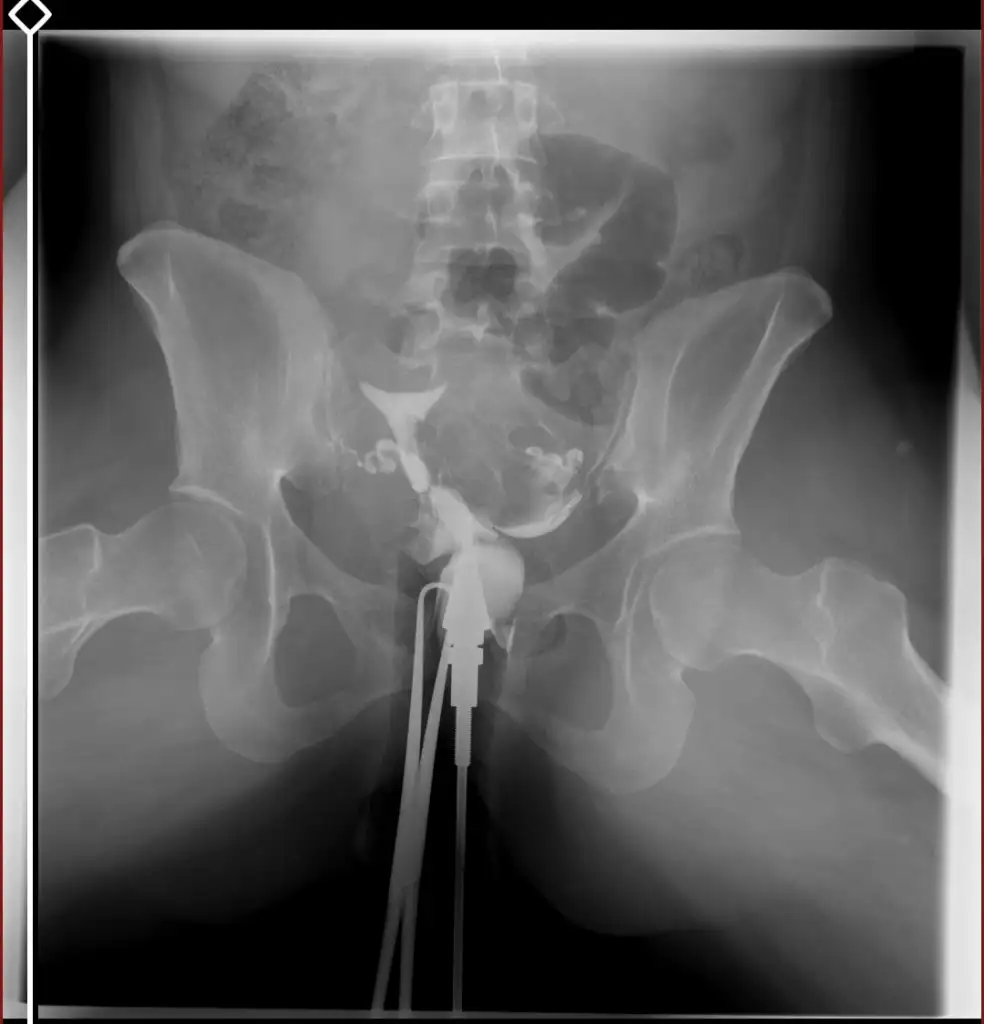

tüp bebek merkezine yönlendirdi . Orada daha detaylı kan tahlili muayene yapıldı adet bitimi hsg çekindim . Çekindiğim gün işlem başında doktor iki tüpün de tıkalı canım dedi ben ağlamaya başladım ağlama sakinleş ilaç ile açmaya çalışacağım eğer olmazsa ameliyat olursun demişti . İşleme 4-5 kez tekrarladık . Sonra iyi kötü bi gidiş oldu . O zaman ki ilgilenen doktora olanları anlattım böyle birşey imkansız tüpler açık o ara kasmışsındır dedi ama hiç kasmadım inanın ki . 6 ay dene olmazsa gel dedi 6 ay sonra gittim o doktor yoktu . Başka doktora geçtim oda sızıntının yeterli olmadığını hala tıkalı olduğunu ve içeriye iyi bir müdahale yapılması gerektiğini söyledi . Ameliyat önerdi . Laparoskopi olacağım ayın 27 sinde . Sonrasında aşılama yapmaya başlıcaz olmazsa